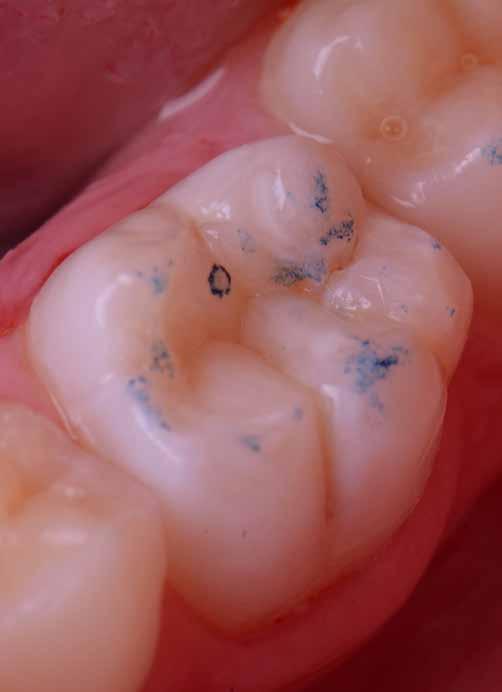

Az 53 éves hölgy páciens jobb felső 6-os fogában látható amalgámtömés cseréje volt a cél. A tömés mellett secunder caries és az amalgám következtében létrejött mesialis zárólécen áthaladó repedés, továbbá mesialis caries figyelhető meg (1. ábra). El kellett kerülni, hogy a tömés kifúrásakor az amalgámtörmelék a páciens szájába kerüljön, esetleg ebből valamennyit lenyeljen, a kezelés első lépésként kofferdám izoláció került fel a jobb felső kvadránsba (2. ábra). A kapocs a 1.7 fogra került, ezzel kényelmesen helyet teremtett a későbbiekben felkerülő matricarendszernek. Az egyszerre több fog izolálása lehetővé teszi, hogy a szomszédos fogak referenciául szolgáljanak a restauráció felépítése közben.

A régi amalgámtömés eltávolítását követően caries indikátor segítette a carieses laesio megfelelő kitisztítását a pulpa expozíciója nélkül. Ezután kerülhetett sor az ideális üregdesign kialakítására, továbbá a zománcszélek finírozására (3. ábra) Az approximális box megnyitása során az alátámasztatlan zománcprizmák eltávolításra kerültek, ezzel is csökkentve a secunder caries képződés veszélyét. Az így kialakuló forma elősegíti a matrica megfelelő adaptációját, végül pedig az approximális box határainak a hozzáférhetőségét, így finírozás során ez jobban kontrollálható és polírozható.

A Palodent V3 matricarendszer felhelyezését követően a zománc 10 másodperces szelektív savazása, majd lemosása és leszárítása után történt a kavítás bondozása Prime & Bond Universallal.

Kulcslépés: a II. osztályú üreget a matricarendszer segítségével I. osztályúvá lehetett átalakítani.

A pontosabb széli záródás érdekében célszerű a matrica illesztési határába némi folyékony kompozitot felvinni (NeoSpectra ST flow A2), majd megvilágítás nélkül a zárólécet paszta kompozittal (NeoSpectra STHV A2) felépíteni, miközben a kifolyó fölösleges folyékony kompozit eltávolításra kerülhet. Így ki lehetett használni és kombinálni a két különböző konzisztencia előnyeit.

A polimerizációt követően kerülhet sor a matricafeszítő gyűrű, valamint a matrica eltávolítására. A Palodent V3 fülekkel ellátott matrica kialakításának és a speciális PinTweezers csipesznek hála, a feszes kontaktpont ellenére a matrica könnyedén eltávolítható. Az éket viszont a kezelés végéig

célszerű bennhagyni, elkerülve egy esetleges nemkívánatos vérzést (4. ábra)

A matrica és gyűrű nélkül az approximális fal magassága, valamint a szomszédos fogakhoz viszonyítható dimenziók jobban megállapíthatóak. A jobb térlátás és a nagyobb mozgástér precízebb eredményhez vezet, csökkentve ezzel az utólagos finírozás mértékét, továbbá a részletgazdagon kialakított anatómiai struktúrák torzulásának az esélyét. Az üreg mélyebb részei SDR Plus A3-mal kerültek feltöltésre, majd NeoSpectra STLV A3-mal kiegészítve vált teljessé a dentin pótlása (5. ábra), ezzel létre lehetett hozni egy homorú formájú kromatikusabb alapot.

Ezt követően csücsökről csücsökre haladva a felső hatosokra jellemző anatómiai struktúrák, megfelelő orientációval bíró csücsöklejtők és elsődleges barázdák Neo Spectra

HV A2 anyagból kerültek kialakításra (6. ábra). Apró „kompozit-hurkákkal” kiegészítve létrehozható a csücskökön belüli tagoltság, ezzel kialakítva a másodlagos barázdarendszert és egy sokkal kidolgozottabb anatómiai struktúrát (7. ábra). A fogorvos esetleges „művészi hajlamát” is figyelembe véve, a természethű megjelenés barázdafestéssel (Micerium - Stain Brown 2) még tökéletesebb lehet (8. ábra). Ezzel a korábban részletgazdagon kialakított ba-